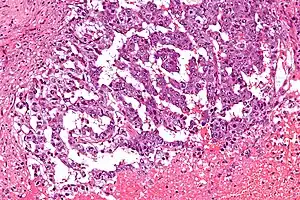

| Micrograph showing the yolk sac component of a mixed germ cell tumour. H&E stain. | |

EST can have a multitude of morphologic patterns including: reticular, endodermal sinus-like, microcystic, papillary, solid, glandular, alveolar, polyvesicular vitelline, enteric and hepatoid.

Schiller–Duval bodies on histology are pathognomonic and seen in the context of the endodermal sinus-like pattern. Rarely, it can be found in the vagina.[5][6]